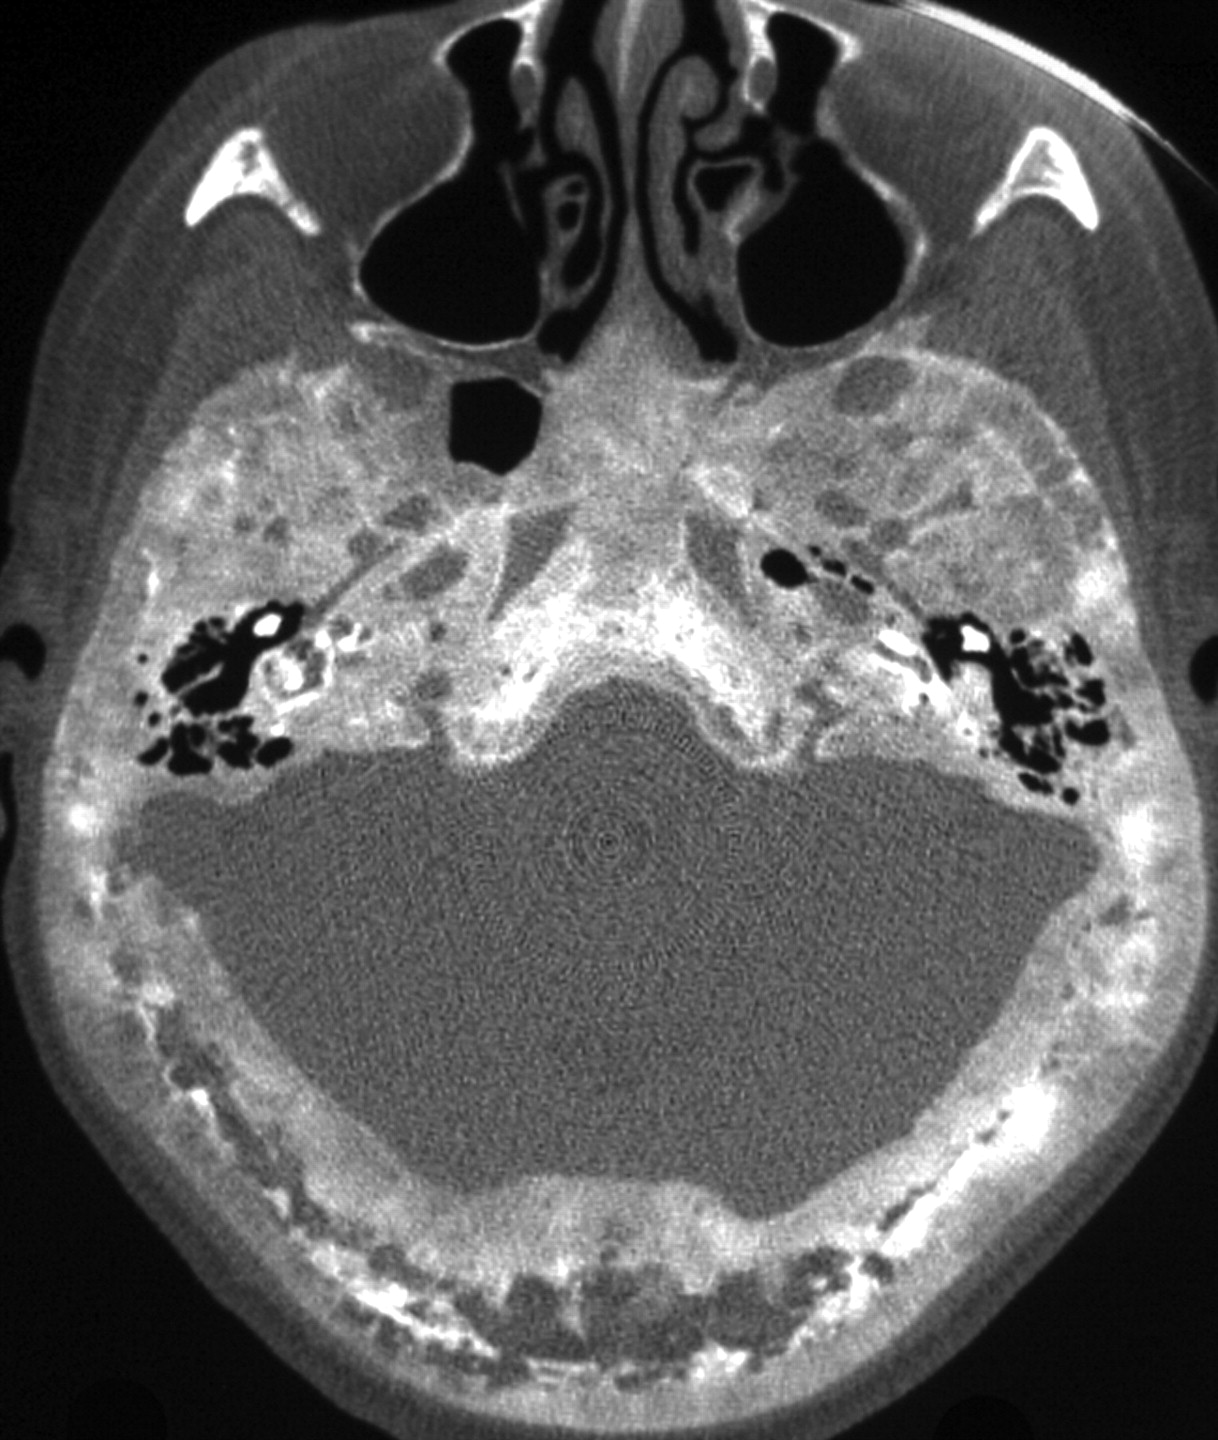

Glomus tumors are vascular paragangliomas located in close proximity to cranial nerves. Glomus tympanicum, the most common tumor of the middle ear cavity, usually arises along the course of the tympanic nerve (Jacobson nerve). Glomus tumors are most frequently located on the cochlear promontory (Fig 1) but can arise almost anywhere in the medial mesotympanum.18 The typical appearance of a glomus tumor on temporal bone CT is a round mass based on the cochlear promontory. On MR imaging, these tumors show intense enhancement. Glomus tympanicum usually does not cause erosion of the underlying bone; if the floor of the middle ear cavity is eroded, a glomus jugulotympanicum should be considered (described in the section on jugular foramen masses). Unlike paragangliomas elsewhere in the body, glomus tumors are usually solitary, and the detection of such a lesion does not indicate a need for further imaging to search for additional tumors.

Glomus tympanicum (arrow) in a 30-year-old woman with right-sided pulsatile tinnitus. Axial CT image demonstrates lobulated soft-tissue attenuation in the middle ear overlying the cochlear promontory.